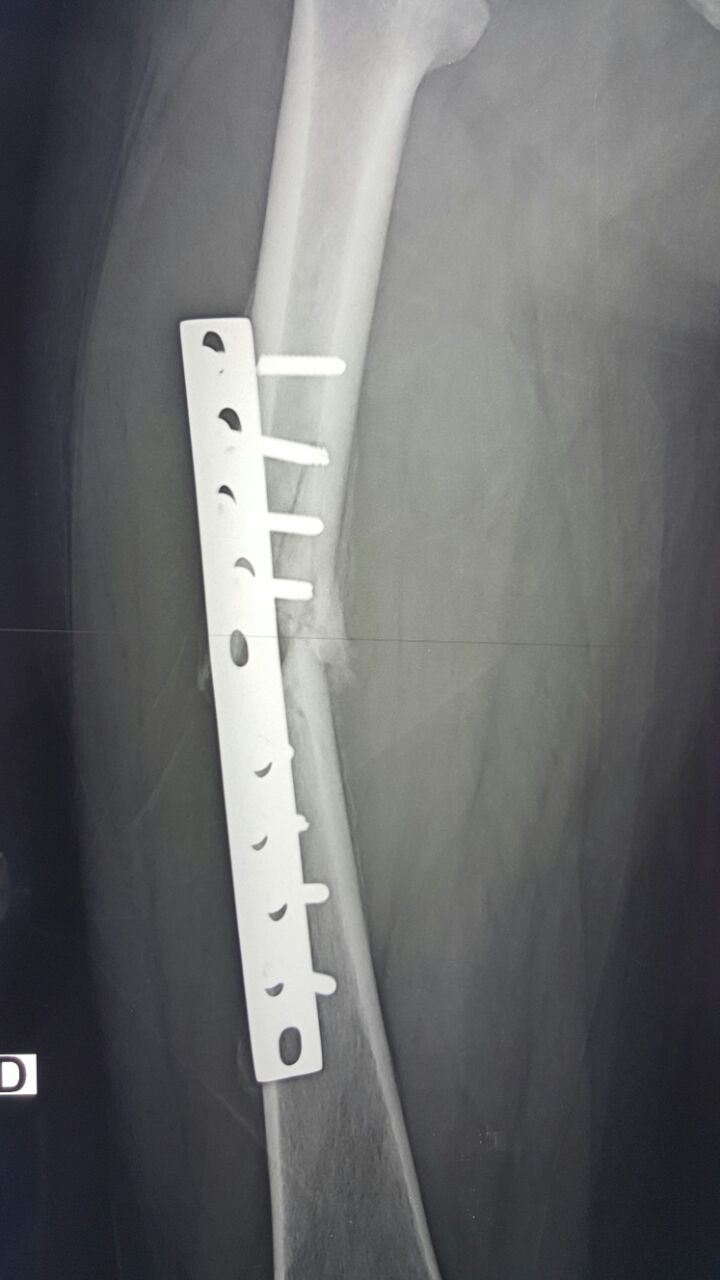

Снимки

А почему Вы решили, что пластина обречена изначально? Сдесь просто была слишком короткая пластина и Недопустимая раняя нагрузка для данного случая. гвоздь, конечно, лучше. Но и пластинку можно. Если все по правилам. А гвозди то же иногда " обрекаются"

image.jpg

потому и обречена, что короткая, недостаточная рабочая длина,в представленном вами случае неадекватный диаметр импланта и , возможно, непроведенная вовремя динамизация(хотя, судя по блокировке овального отверстия в статике, возможности динамизации и не предполагалось). А чтобы синтезировать LC-DCP такие диафизарные переломы, надо ОЧЕНЬ сильно их(пластны) любить, а больных наооборот - не очень

Есть, конечно, показания и для остеосинтеза пластиной переломов бедра, однако, данный случай, похоже, не из этой категории.

Правильно и то, что на настоящий момент мы имеем дело с несросшимся переломом бедренной кости и несостоятельным остеосинтезом.

Мне бы казалось правильным в данном конкретном случае удалить металл (уж не знаю, насколько малоинвазивно, учитывая перелом винтов) и выполнить остеосинтез толстым стержнем с рассверливанием канала.

Пластина конечно короткая. На мой взгляд она выдержала бы минимальную нагрузку ,т.е. при фактически полном обездвиживании, которое сопряжено с постельным режимом, но тогда смысл остеосинтеза без активизации? Что касается выбора импланта, то блокируемый гвоздь IMHO более предпочтителен,опять же ранняя нагрузка. Или тогда уж широкая LCP на 10 отверстий, если нет гвоздя, желательно по MIPO, хоть и частично. Стандартная LC-DCP все-таки уже устарела. С уважением.